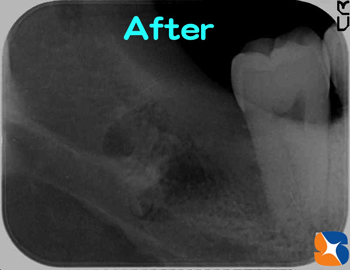

奥深い横向きの親知らず

コラム「奥深い横向きの親知らず」の画像